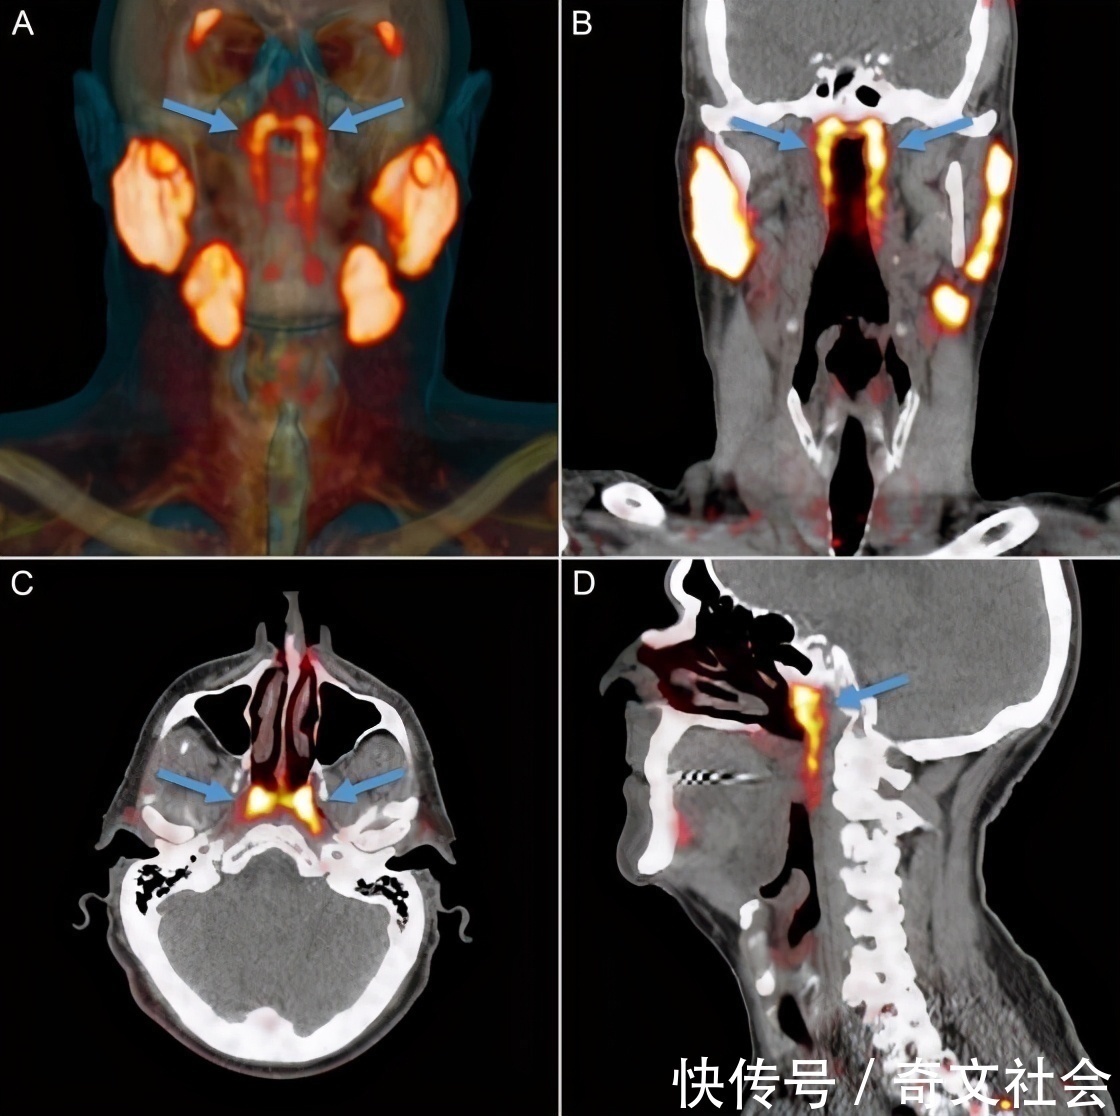

喉咙深处发现新器官

这是在人类发现手臂动脉增多,进化之后的一个新发现。是科学家在《放射疗法与肿瘤学》杂志上发表的研究,这个新器官是位于喉咙区域,器官平均约1.5英寸长(3.9厘米),发现者们称它为“隆凸唾液腺”。如今人类有三个已知的唾液腺:一个在舌下,一个在下颚下,还有一个在脸颊后部的下颚的后面。除此之外,就是一些极小的唾液腺。